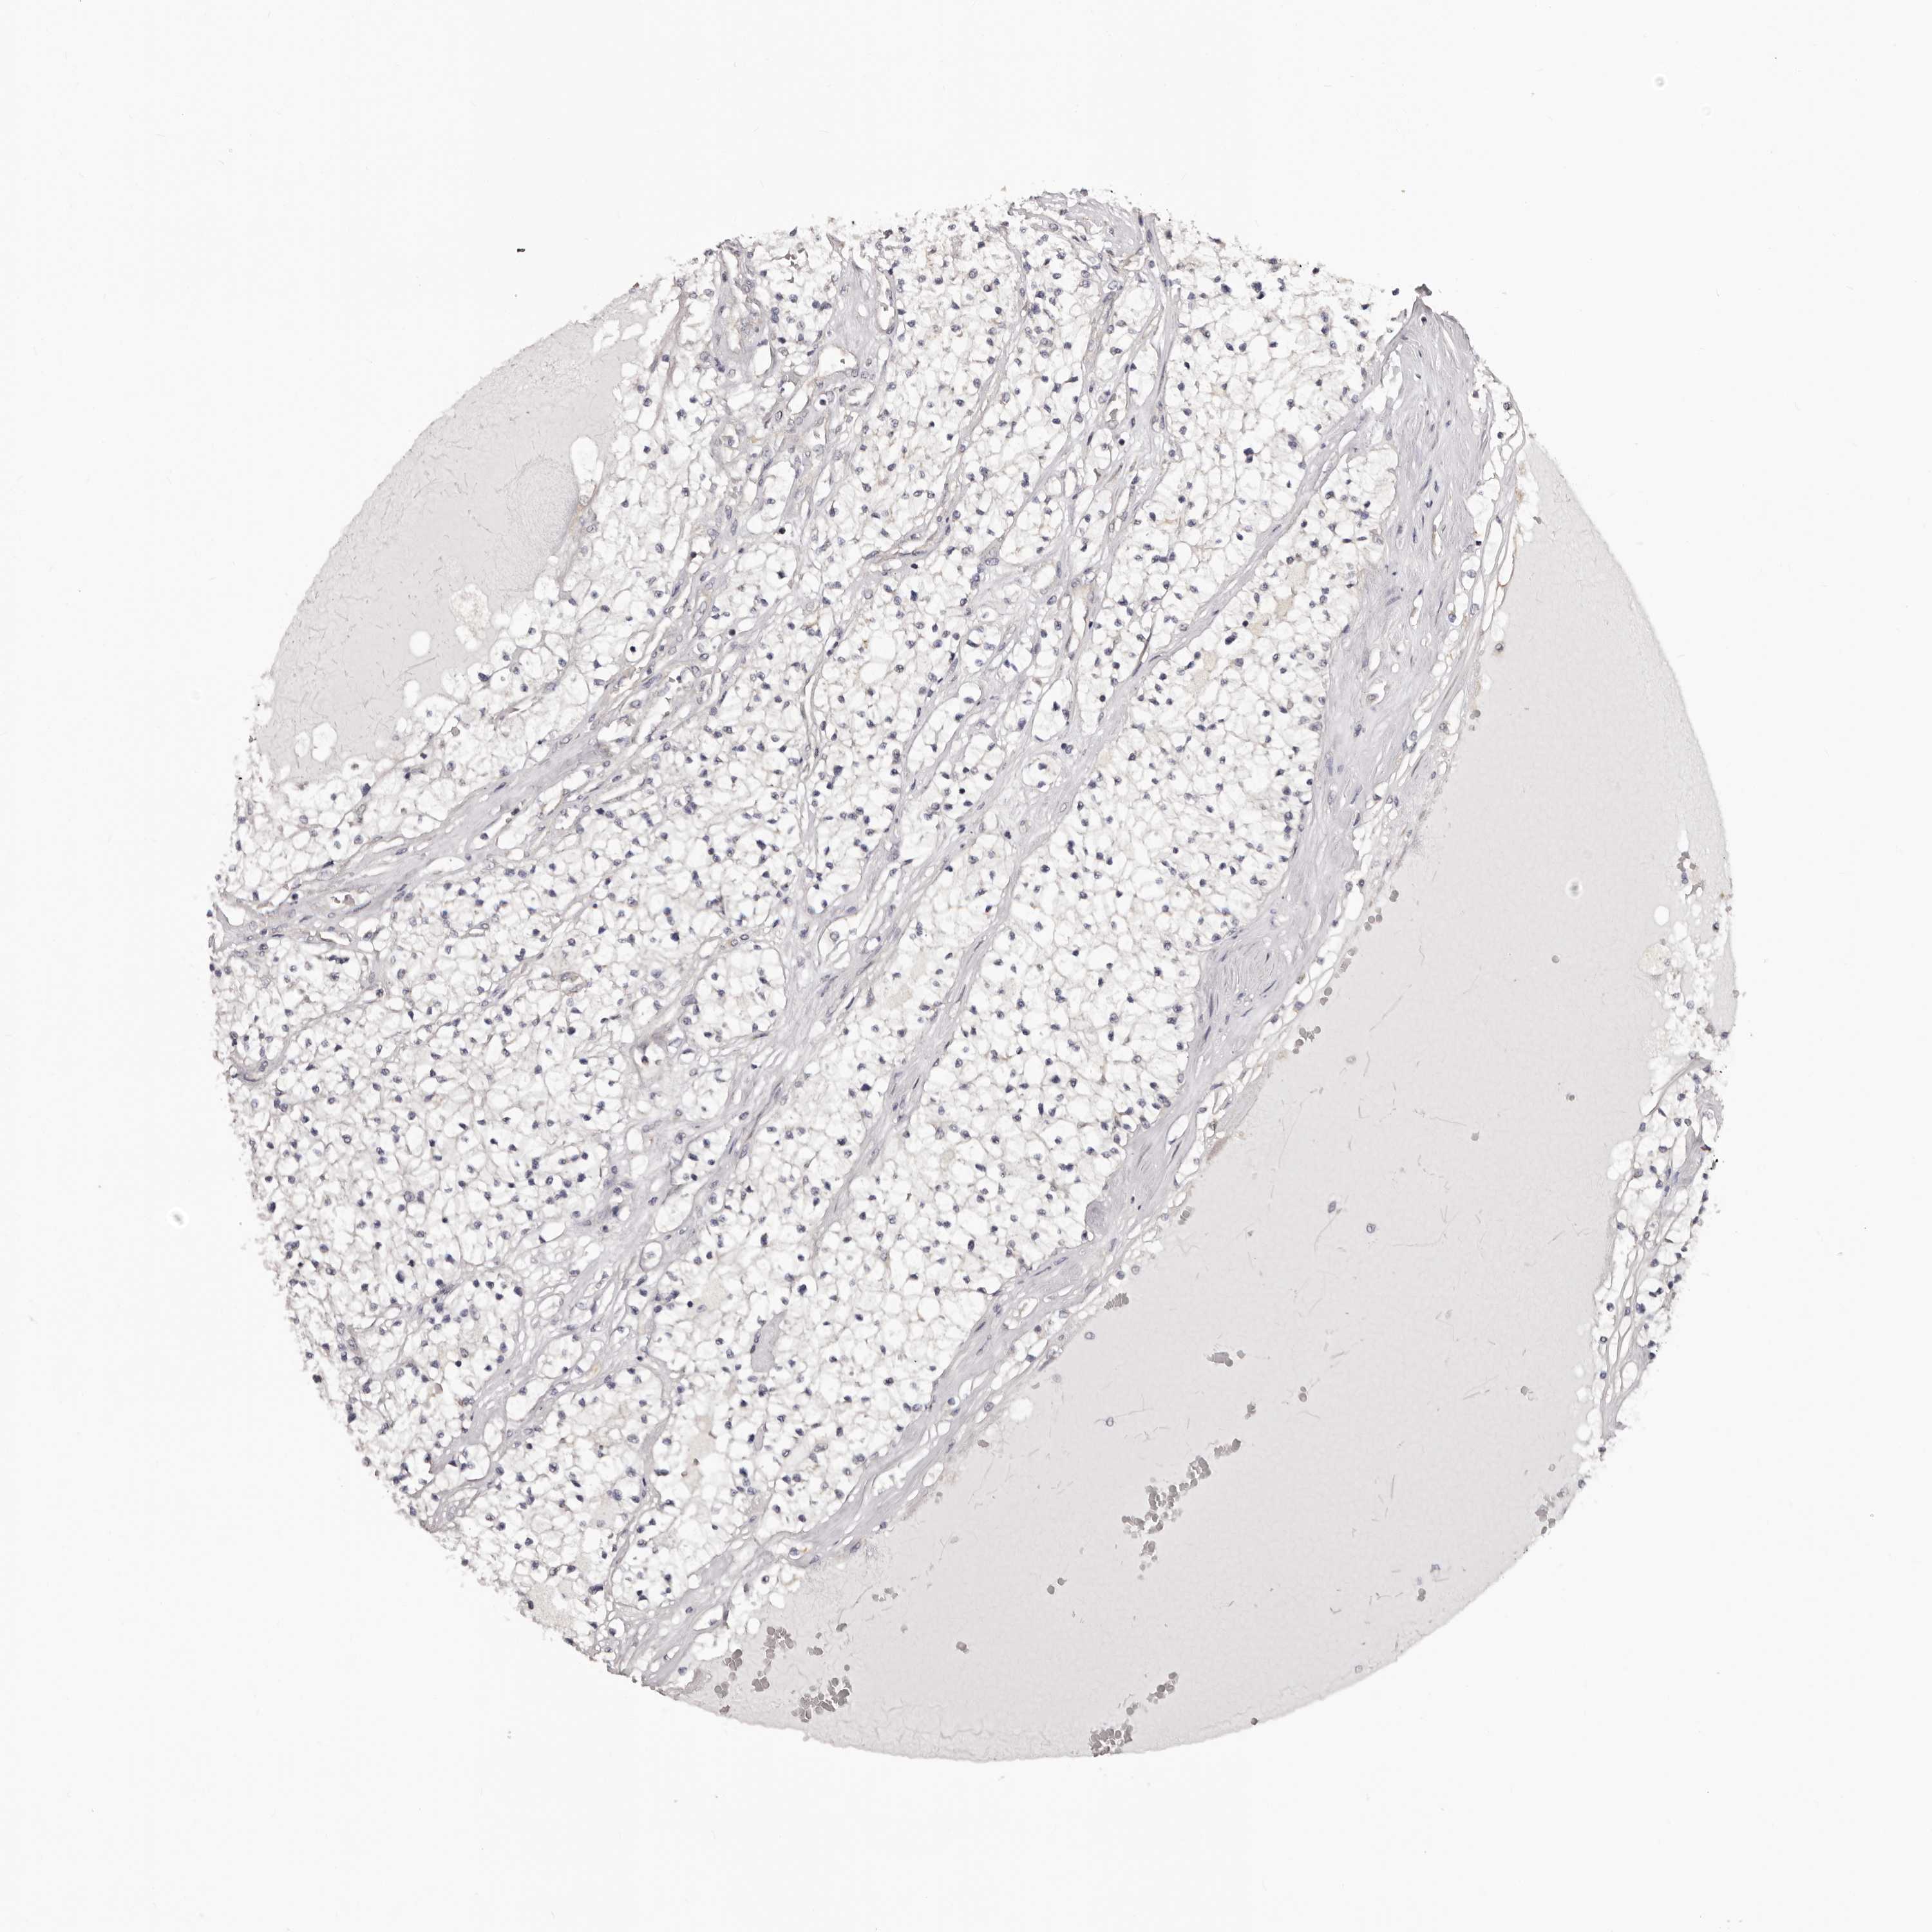

KIDNEY RENAL CLEAR CELL CARCINOMA (VALIDATION) - Interactive survival scatter ploti

The Survival Scatter plot shows the clinical status (i.e. dead or alive) for all individuals in the patient cohort, based on the same data that underlies the corresponding Kaplan-Meier plots. Patients that are alive at last time for follow-up are shown in blue and patients who have died during the study are shown in red.

The x-axis shows the expression levels (FPKM) of the investigated gene in the tumor tissue at the time of diagnosis. The y-axis shows the follow-up time after diagnosis (years). Both axes are complimented with kernel density curves demonstrating the data density over the axes. The top density plot shows the expression levels (FPKM) distribution among dead (red) and alive patients (blue). The right density plot shows the data density of the survived years of dead patients with high and low expression levels respectively, stratified using the cutoff indicated by the vertical dashed line through the Survival Scatter plot. This cutoff is automatically defined based on the FPKM cutoff that minimizes the p-score. The cutoff can be changed by dragging the vertical line or by entering a cutoff value in the square labeled "Current cut-off".

Under the Survival Scatter plot the p-score landscape (black curve; left axis) is shown together with dead median separation (red curve; right axis). Dead median separation is the difference in median mRNA expression between patients who have died with high and low expression, respectively. It is calculated as follows: median FPKM expression of dead patients with high expression - median FPKM expression of dead patients with low expression. This is intended to aid the user in visually exploring custom cutoffs and the associated p-scores and dead median separation.

Individual patient data is displayed and can be filtered by clicking on one or more of the category buttons on the top of the page. Categories describing expression level and patient information include: high, low, alive, dead, female, male and tumor stages. The scale of the x-axis can be toggled between linear and log-scale by clicking on the "x log" button. Mouse-over function shows TCGA ID, patient information and mRNA expression (FPKM) for each patient.

& Survival analysisi

Kaplan-Meier plots summarize results from analysis of correlation between mRNA expression level and patient survival. Patients were divided based on level of expression into one of the two groups "low" (under cut off) or "high" (over cut off). X-axis shows time for survival (years) and y-axis shows the probability of survival, where 1.0 corresponds to 100 percent.

NOL12 is not prognostic in Kidney Renal Clear Cell Carcinoma (validation)

Best expression cut offi

Based on the FPKM value of each gene, patients were classified into two groups and association between prognosis (survival) and gene expression (FPKM) was examined. The best expression cut-off refers the FPKM value that yields maximal difference with regard to survival between the two groups at the lowest log-rank P-value. Best expression cut-off was selected based on survival analysis .

When clicking on this number, the vertical dashed line indicating cut-off, the interactive survival plot, and the Kaplan-Meier curve will be adjusted to show results based on the best expression cut-off.

: 18.85

P scorei

Log-rank P value for Kaplan-Meier plot showing results from analysis of correlation between mRNA expression level and patient survival.

N/A

TCGA RNA samplesi

RNA-seq data is reported as average FPKM (number Fragments Per Kilobase of exon per Million reads), generated by the The Cancer Genome Atlas (TCGA) .

Normal distribution across the dataset is visualized with box plots, shown as median and 25th and 75th percentiles. Points are displayed as outliers if they are above or below 1.5 times the interquartile range. FPKM values of the individual samples are presented next to the box plot.

Average pTPM 15.2

Number of samples 100